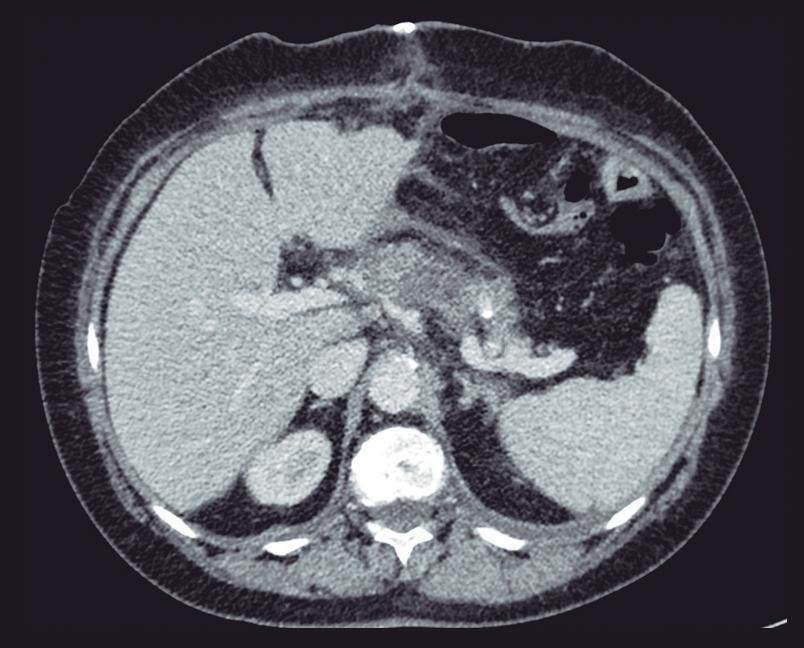

La endoscopía superior es un procedimiento fundamental para el diagnóstico, la evaluación de la respuesta al tratamiento y el monitoreo a largo plazo de la actividad de la EEo. Los hallazgos endoscópicos típicos incluyen edema (reducción de vascularidad), anillos esofágicos fijos, exudados blancos, surcos longitudinales, estenosis, estrechamiento de la luz esofágica, friabilidad de la mucosa (mucosa en papel crepé) y una consistencia firme de la mucosa al realizar biopsias (signo de “tracción" o "resistencia”) en pacientes con fibrosis (Figura 1). Estos hallazgos no son patognomónicos y no constituyen un criterio diagnóstico; sin embargo, cuando se evalúa de forma cuidadosa, en la gran mayoría de los casos se pueden observar.19-21

En el panel A se observa un esófago con edema difuso y pliegues longitudinales; en el panel B se aprecia edema con pliegues y exudados blanquecinos; en el panel C se evidencia un estrechamiento luminal acompañado de anillos esofágicos y exudados; y en el panel D se muestra un desgarro mucoso posterior a la dilatación con bujía de Savary, hallazgo esperado tras este procedimiento terapéutico.

Figura 1. Características endoscópicas de la esofagitis eosinofílica